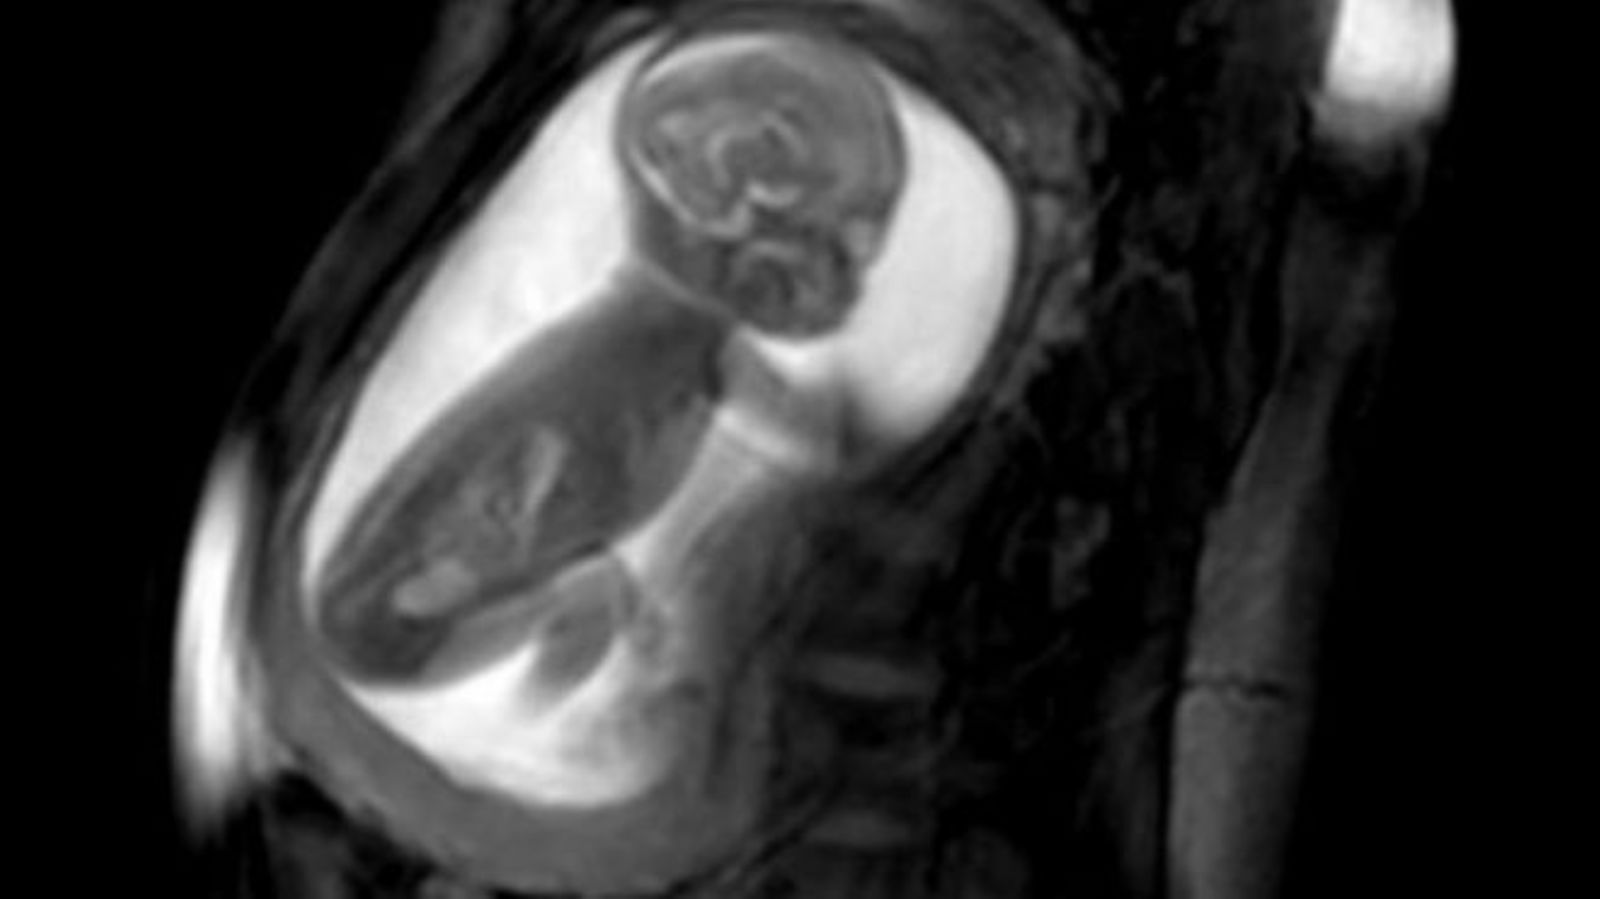

تقنية تصوير تساعد في تشخيص أمراض قلب الأجنة

توصل باحثون لطريقة تساعد في تشخيص أمراض القلب لدى الأجنة وعلاجها فور ولادة الطفل، وذلك عن طريق التقاط صور لقلب الجنين وهو ينبض داخل رحم الأم، حيث يتم فحص النساء الحوامل بجهاز تصوير الرنين المغناطيسي وأجهزة كمبيوتر فعالة تستطيع رسم نماذج ثلاثية الأبعاد، لقلوب الأجنة الصغيرة، وذلك وفقا لموقع BBC.

ويقول الباحثون أن قلب الجنين صغير للغاية، وينبض بسرعة مذهلة، كما أن الجنين يتحرك داخل الرحم، لذلك فإن تصوير القلب يبدو غير واضح تماما، لكن جاءت هذه الأداة التي تلتقط سلسلة صور ثنائية الأبعاد للقلب من زوايا مختلفة، وتستطيع برامج الكمبيوتر المتطورة جمع الصور معا، وضبطها من خلال ضربات القلب ثم إنشاء صورة ثلاثية الأبعاد غير مسبوقة للقلب بالكامل، ومن ثم فهي تقدم للأطباء رؤية واضحة للخلل في القلب.